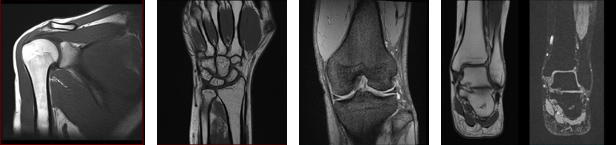

○四肢